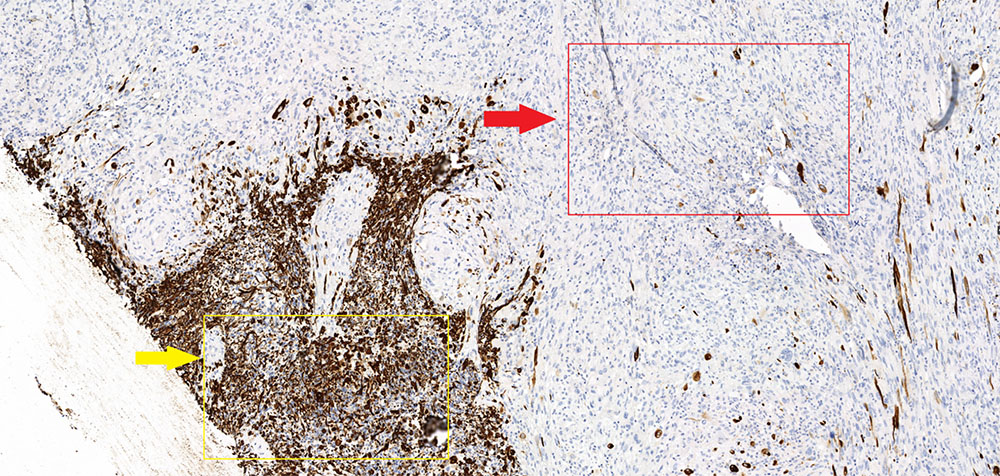

Глиосаркома  (послеоперационный препарат), окраска гематоксилином и эозином, увеличение х10. Глиальная часть демонстрирует выраженный ядерный полиморфизм и клеточную атипию. Саркоматозная часть представлена веретеновидной формы клетками с ретикулиновыми волокнами (соединительная (мезенхимальная) ткань).

Маркер GFAP (специфичный глиальный фибриллярный кислый белок) – демонстрирует характерную выраженную экспессию в глиальной части опухоли (желтая стрелка) и полное отсутствие экспрессии в саркоматозной (красная стрелка). Кроме того в данном микропрепарате стоит отметить отчетливое преобладание саркоматозной части над глиальной.

N.В.! В зависимости от количества саркоматозной и глиальной ткани отмечаются вариации, при этом если саркоматозная ткань преобладает, то опухоль подобна метастазу (хорошо отграниченная и плотная), в случае превалирования астроцитарного(нейроглиального) компонента опухоль идентична классической глиоблатоме (Louis DN, Ohgaki H).